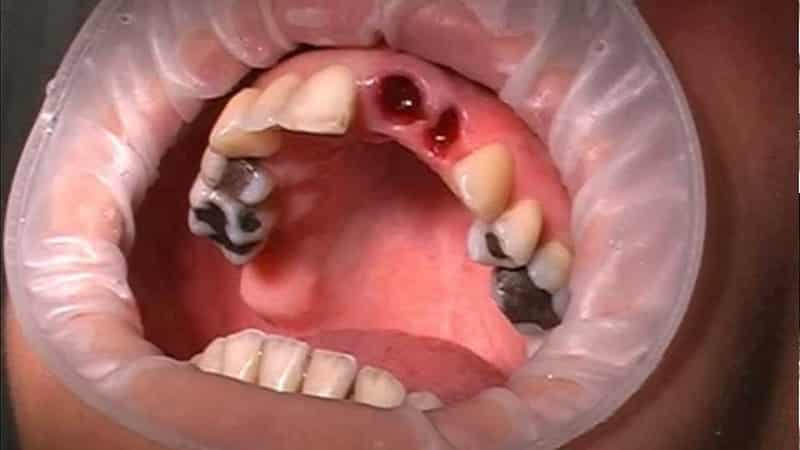

Операция по удалению зуба выполняется, когда консервативное лечение неэффективно. Неприятные последствия могут возникнуть, если:

- зуб сильно болел при удалении;

- на корне образовалась киста, которую удаляли из кости;

- в процессе операции зуб сломался на несколько частей, которые врач удалял по частям;

- общая гигиеническая ситуация в полости рта плохая, с налетом на зубах и образованием зубных камней;

- в процессе операции были обнаружены хронические заболевания полости рта и органов ЛОР;

- болезни пародонта находились в острой фазе;

- врач не соблюдал принципы операции и недостаточно обработал рану;

- были хронические заболевания соседних зубов.

Осложнения после операции по удалению зуба развиваются достаточно быстро. Первые клинические симптомы становятся заметными уже к вечеру после операции. Далее мы рассмотрим наиболее распространенные осложнения после удаления зуба.